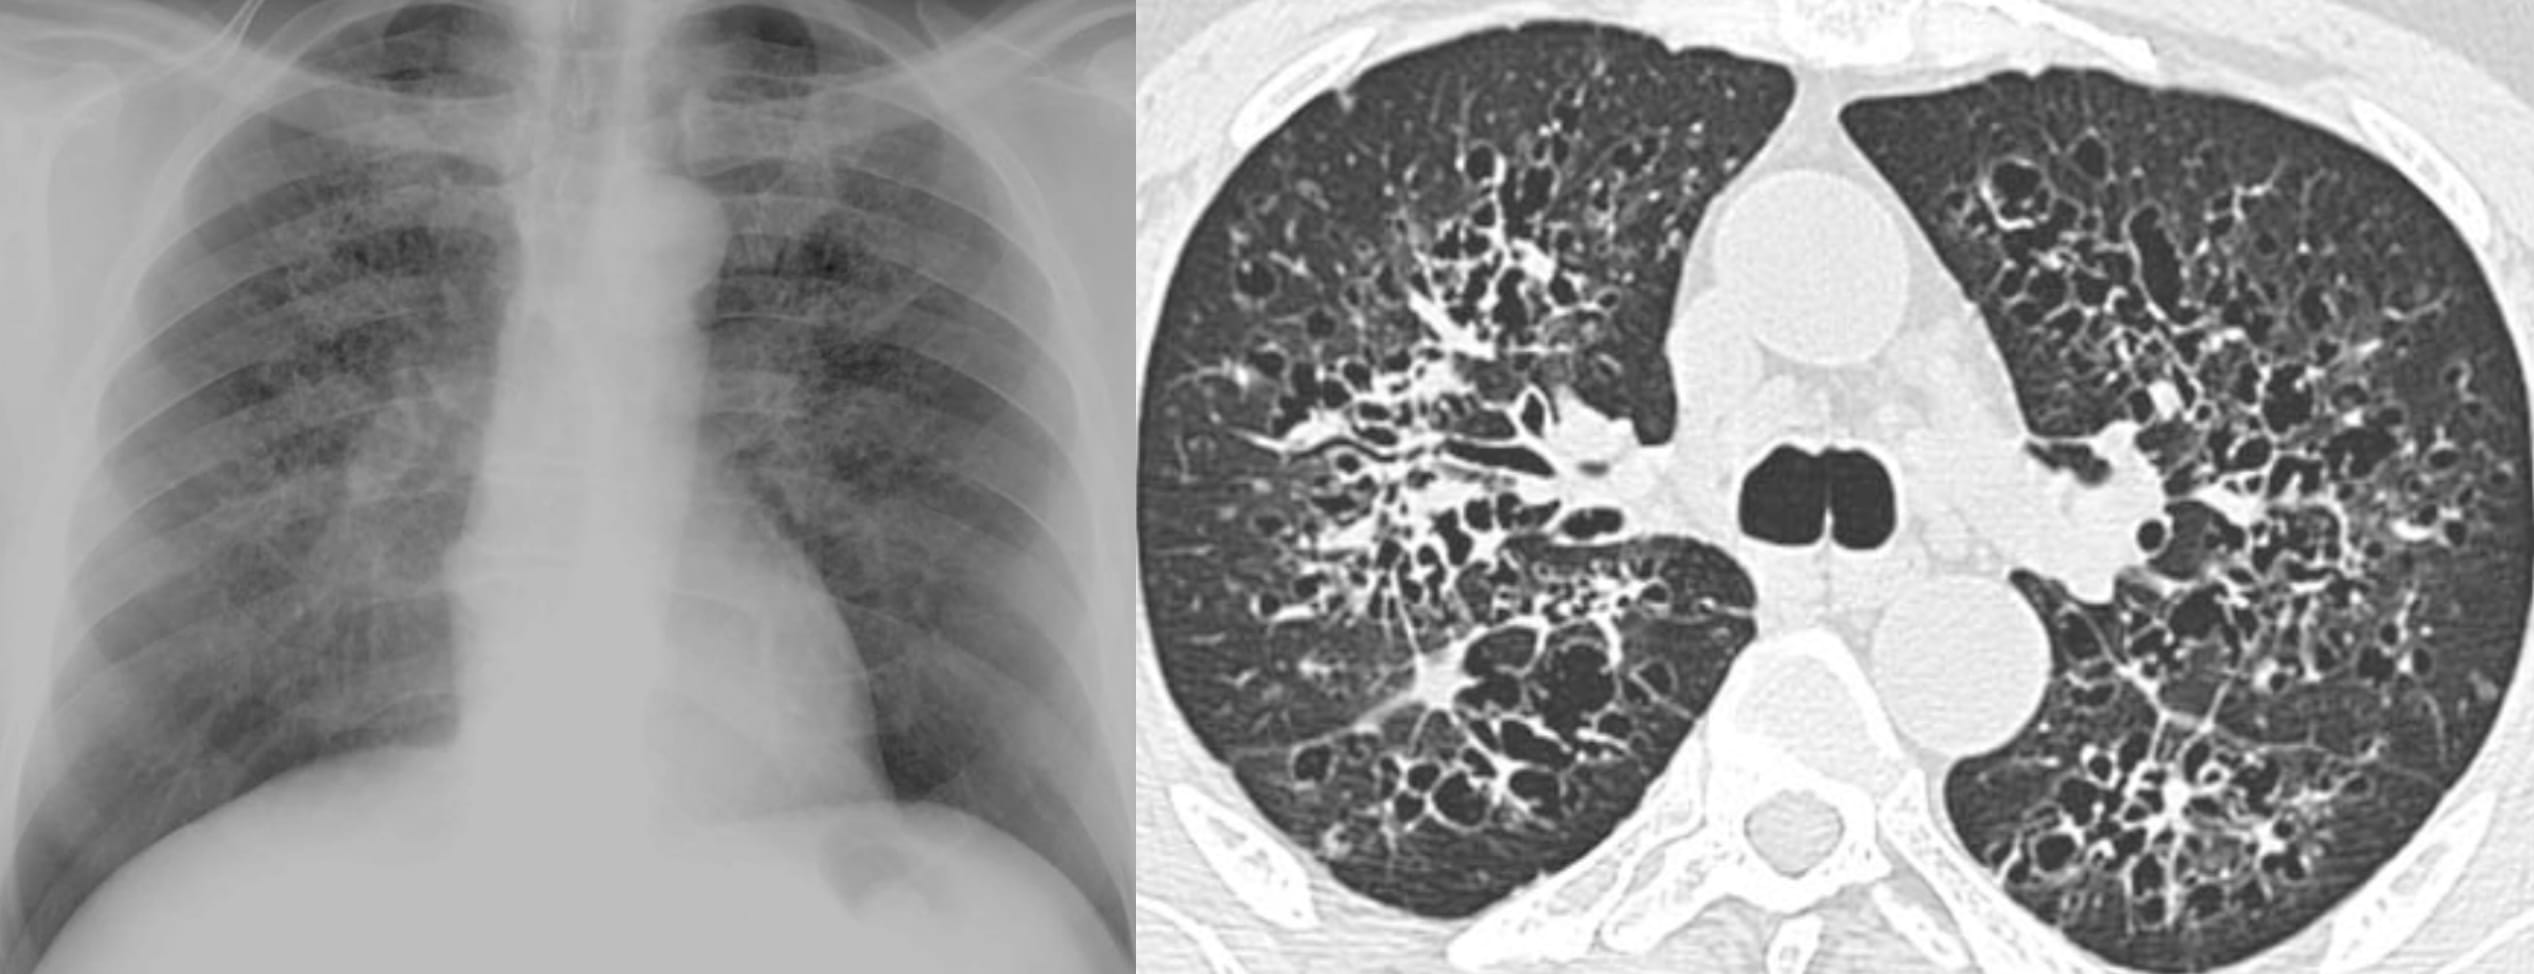

What are Langerhan’s Cells ?

The evolution of pulmonary histiocytosis (PLCH) accounts for the imaging findings:

Key Points

Note the predominant involvement of the upper lungs.

The very definition of an Aunt Minnie